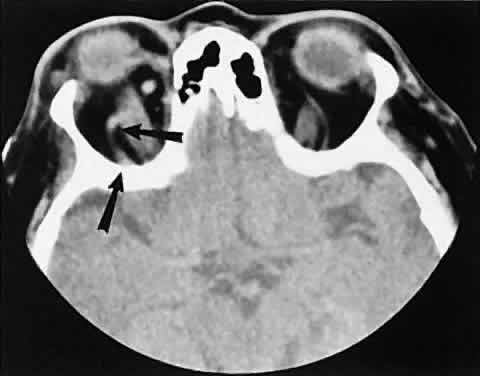

| The edema and inflammatory infiltrate that accompany infections are indistinguishable

from that associated with orbital inflammations. The presence

of sinus disease, however, is a more constant feature with infections, because

the sinus represents the infectious nidus in most cases (Fig. 9). In addition to the frequent appearance of sinus disease, the adjacent

EOM is invariably enlarged. Less often, orbital infections may be transmitted

through the blood, related to a retained foreign body, or spread

from the lids. Chandler and colleagues47 classified orbital infections into five groups. Group 1 (preseptal cellulitis) represents

inflammatory edema and reflects congestion of venous

outflow. Group 2 has actual orbital infiltration/edema with mass effects

and functional deficits. Group 3 includes patients with subperiosteal

abscesses. Most of these dome-shaped subperiosteal abscesses are

located along the medial wall. Group 4 includes patients with orbital

abscesses who may display a ring-enhancing lesion with mass effect. Group 5 represents

intracranial extension of the inflammation into the

cavernous sinus or sinuses, which appear engorged and opacified. Harris48 related the clinical course of patients with subperiosteal abscesses to their CT scans. The sub-periosteal material could not be predicted from the size or the relative radiodensity of the collections on the scan. Serial scans also showed enlargement of the abscess during the first few days of intravenous antibiotic therapy, regardless of the ultimate response to therapy. |